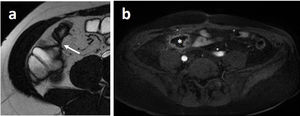

Biphasic contrast (PEG)-enhanced MRE images in a subject with Crohn’s disease with inflammatory stricture of an ileum segment. Note also the dilation of the segment proximal to the stenosis. a) T2-weighted SSFP sequence. The bowel lumen is hyperintense (positive contrast). b) T1-weighted sequence with IVC. The bowel lumen is hypointense (negative contrast), which facilitates the assessment of mural enhancement (arrow) and mesenteric hypervascularisation known as the “comb sign” (asterisk).